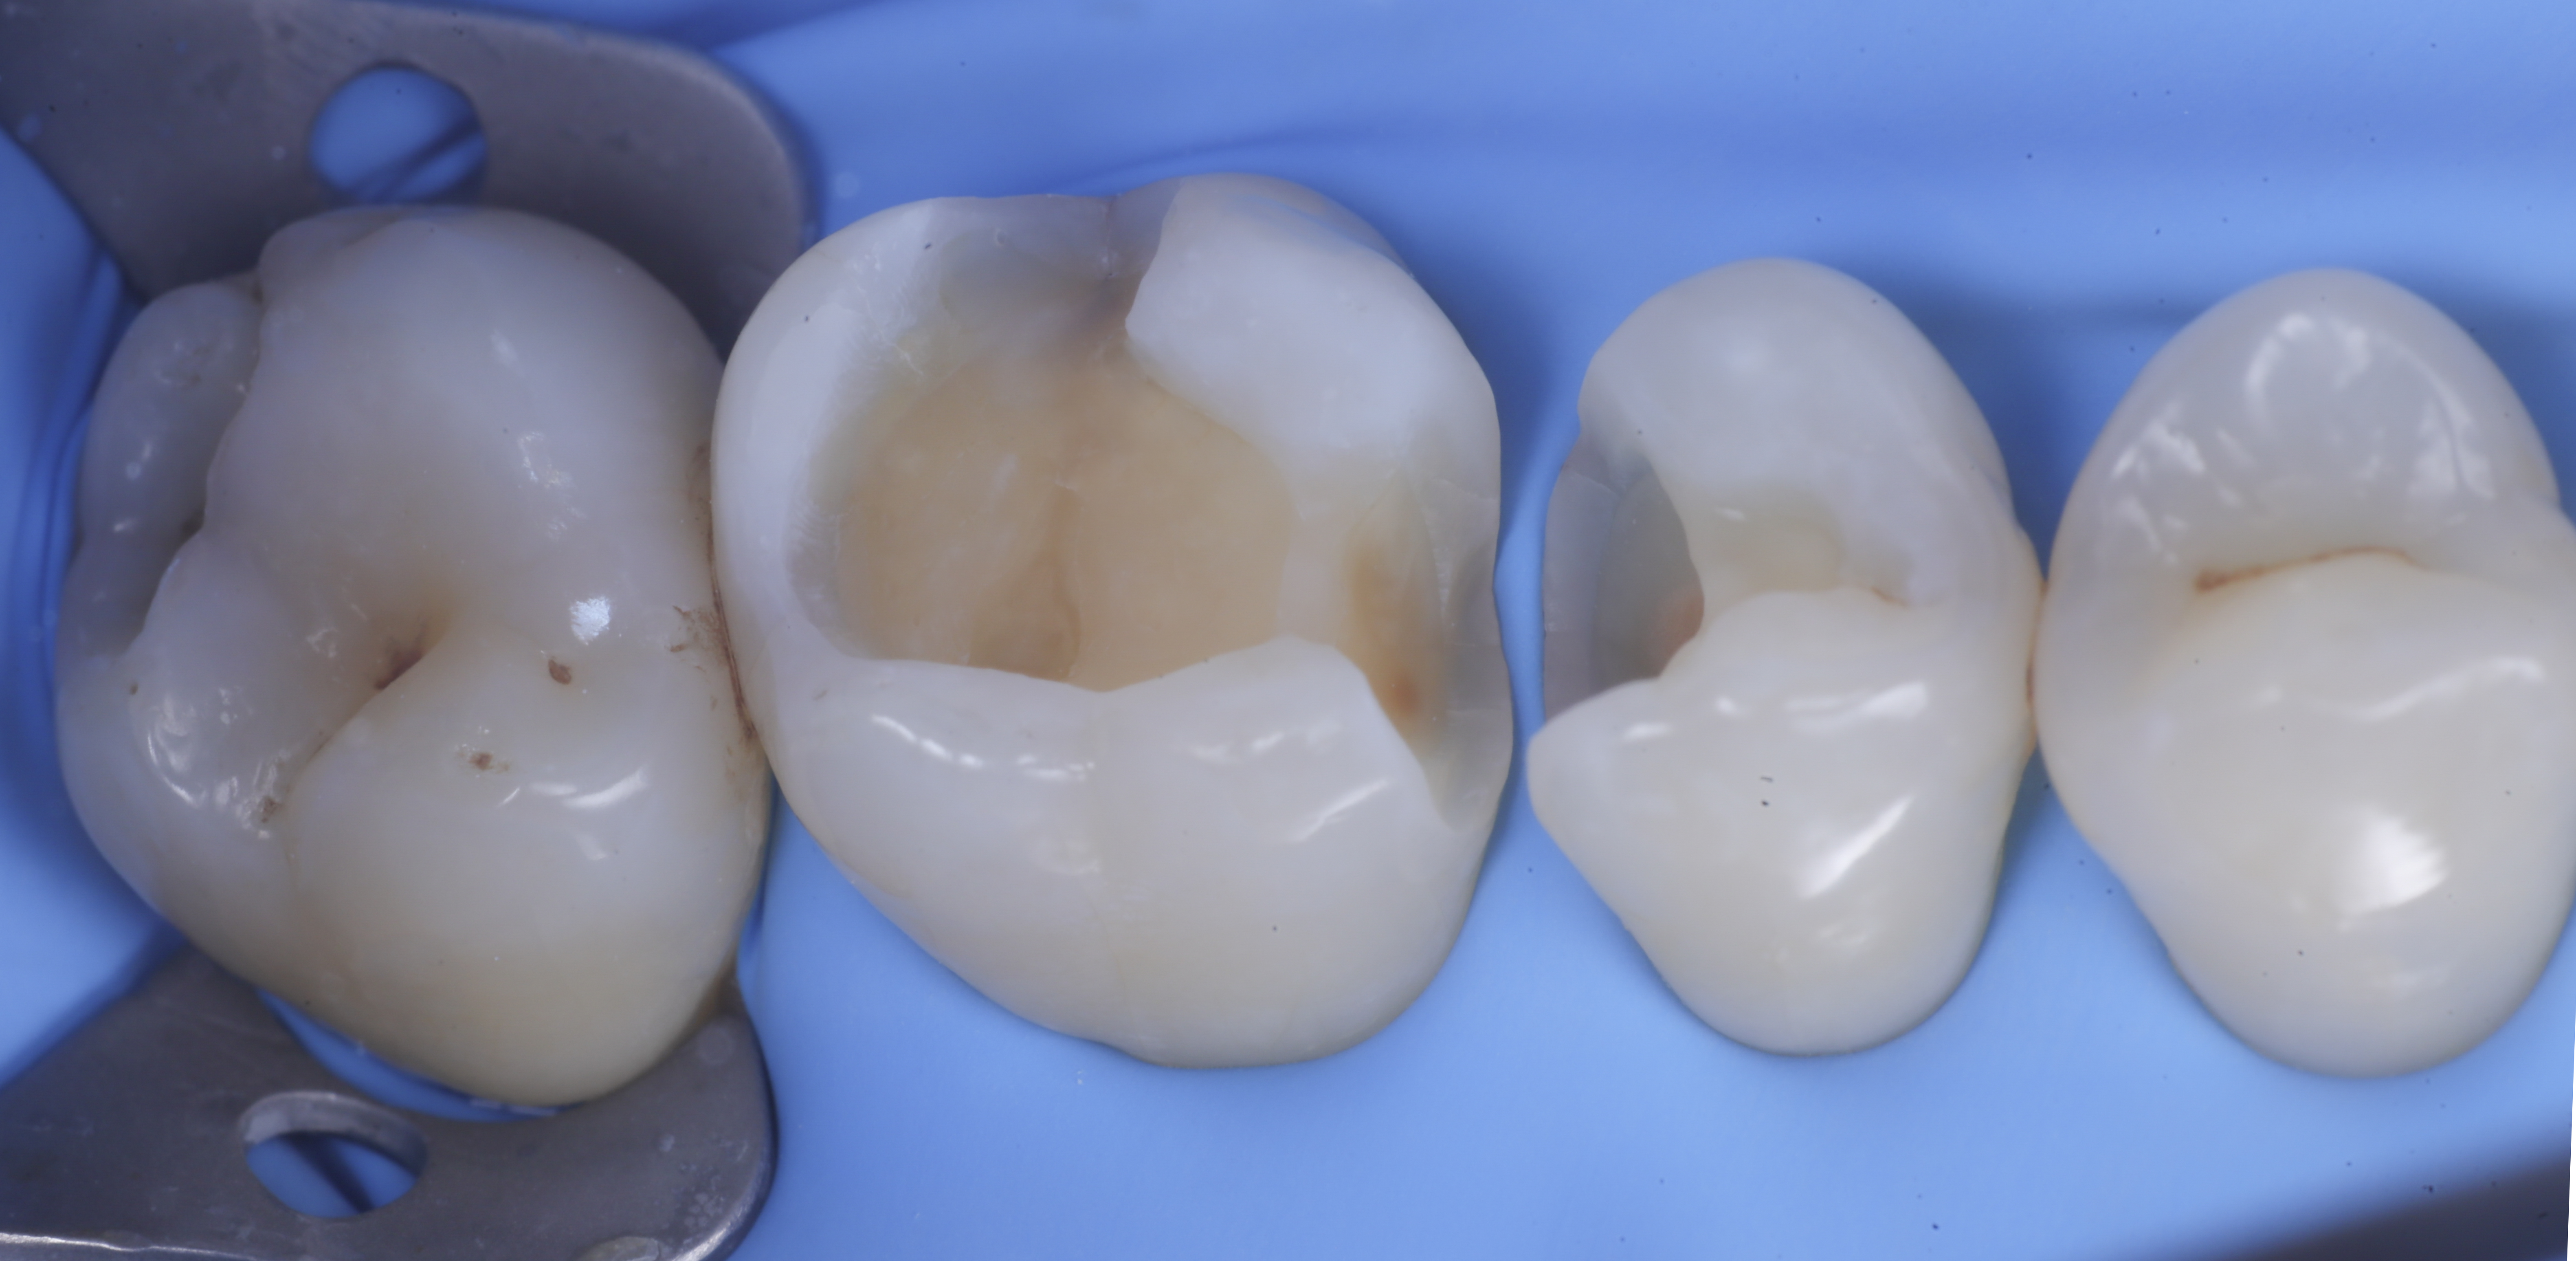

foto 2 Isolamento e aspetto delle cavità ultimate

Una volta eliminato completamente il composito, si procede con la detersione della dentina con frese multilama ed alla rifinitura dei margini di smalto che dovranno essere robusti e puliti.

Dopo il posizionamento del cuneo, anello e delle due matrici sezionai, selezionate per altezza e raggio di curvatura, si procede con l’applicazione dell’adesivo universale, previa pre-mordenzatura dello smalto.